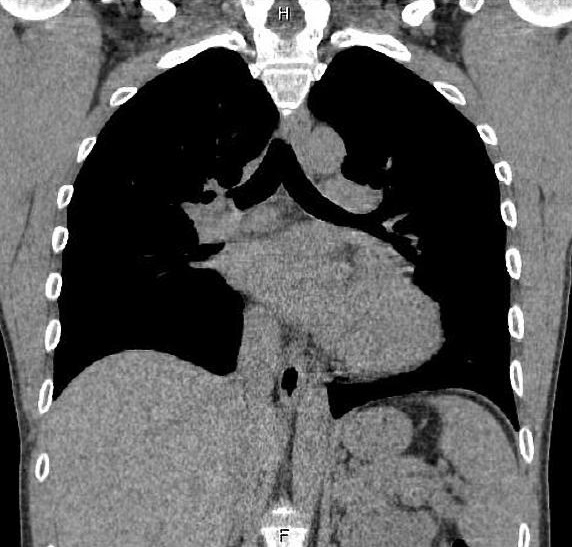

Opacite

d' origine pleurale : Image TDM

- En haute : Empyème et abces

- En bas : Mesotheliome

maligne mais envahis la paroi thoracique .

La

TDM et IRM être faciliter le diagnostic

topographique tumoraux et la présence ou non du

liseré graisseux. La TDM ou IRM avec injection de

produits de contraste se donne de déduire des gammes

étiologiques pafaite :

Les opacités pleurales

dues aux épanchements sont habituellement en «

goutte » avec raccordement obtus en haut et aigu en

bas. Quand ils ne sont pas évidents en standard, ils

sont affirmés en TDM par le signe du « split pleura

»: le produit de contraste souligne la division des

deux feuillets pleuraux viscéral et pariétal, autour

de l'empyème. La distinction avec l'abcès pulmonaire

(sphérique et avec bronchogramme) est aisée